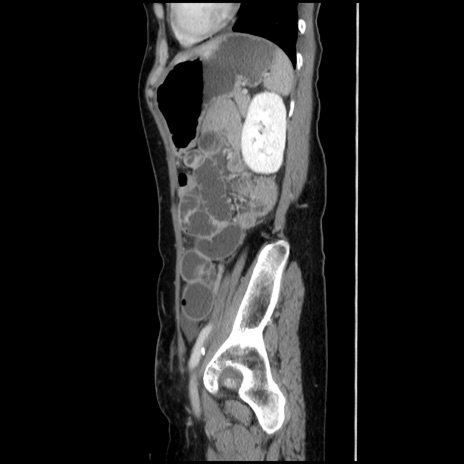

症例32(矢状断像)

【症例】40歳代 女性

【主訴】上腹部痛、嘔気・嘔吐

【現病歴】約9時間前頃から急に上腹部痛、嘔気、嘔吐が出現。改善しないため救急要請。

【既往歴】子宮頚癌(広汎子宮全摘術、放射線療法)、腸閉塞

【身体所見】腹部:平坦、軟、腸雑音亢進、上腹部を中心に腹部全体に圧痛あり。

【データ】WBC 8400、CRP 0.03